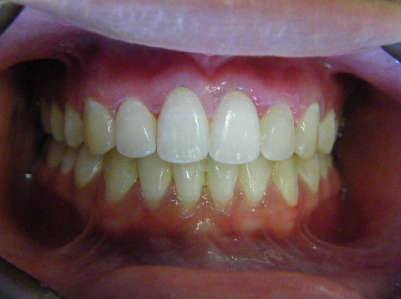

Patient 4: Upper and lower crowding and a deep overbite.